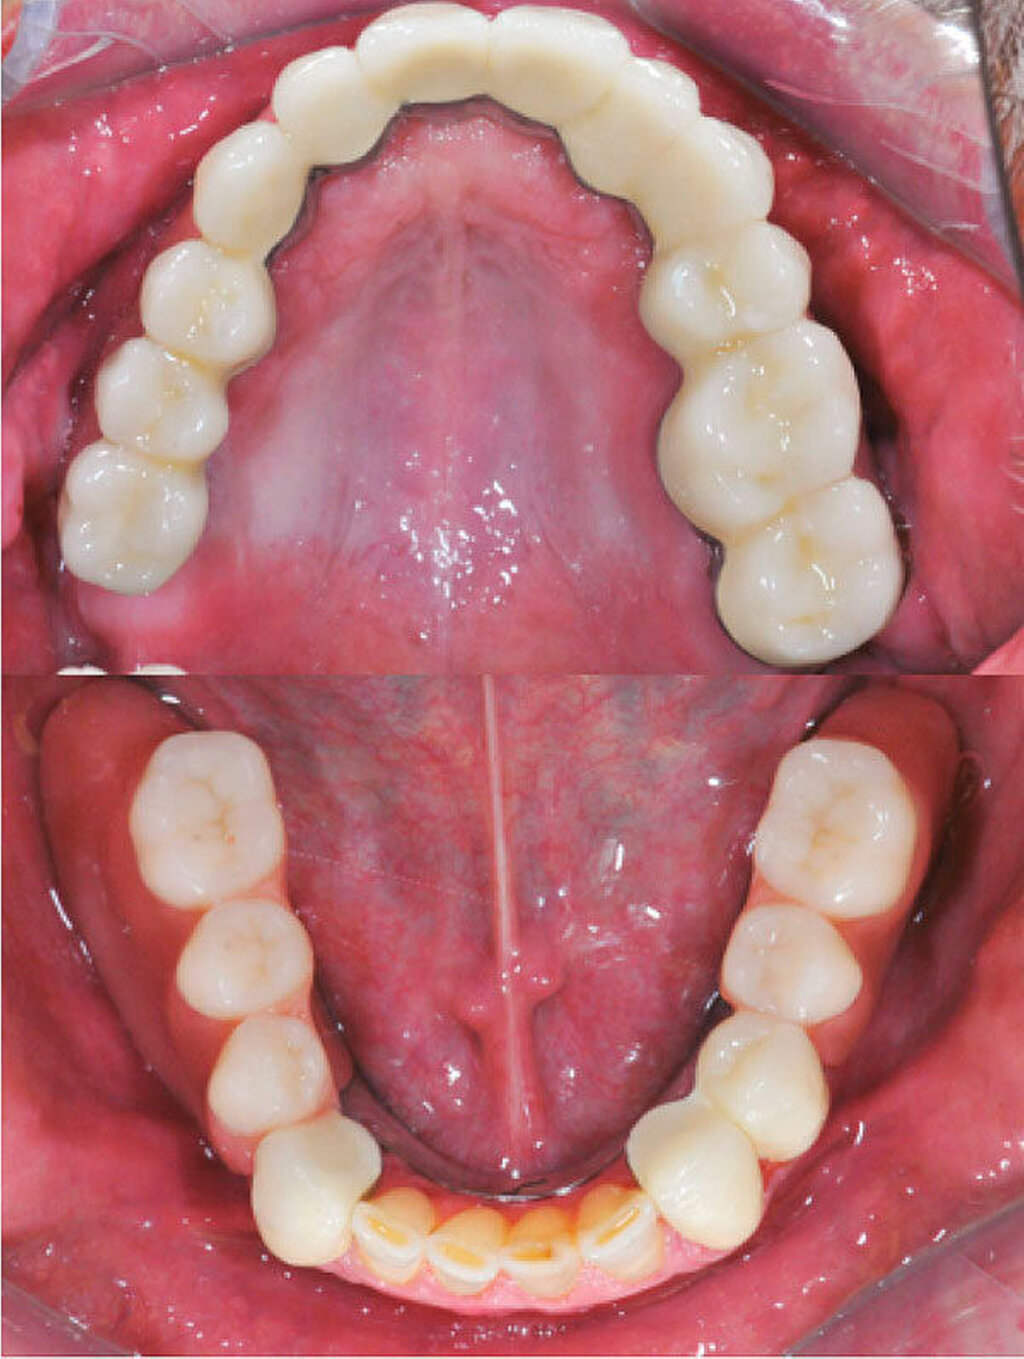

Die klinische Situation zeigte einen atrophierten, teilbezahnten Oberkiefer (herausnehmbarer, nicht implantatgetragener Zahnersatz) sowie einen teilbezahnten Unterkiefer (herausnehmbarer, mit Klammern verankerter Interimszahnersatz) (Abbildung 1). Vor allem fiel der prothetisch eingestellte Kopfbiss im Frontzahnbereich mit ausgeprägter negativer sagittaler Stufe bei einer Rücklage des Oberkiefers von 0,8 cm auf. In der alio loco angefertigten prä-implantologischen Röntgendiagnostik mittels Panoramaschichtaufnahme war dies nicht zu erkennen. Aufgrund des klinischen Bildes eines defizitären Mittelgesichtsprofils erfolgte eine kephalometrische Analyse. Hier bestätigten die ermittelten Werte eine maxilläre Retrognathie (Angle-Klasse III; Abbildung 2).

Nach unauffälliger Heilung ohne Komplikationen und Korrektur der Kieferrelation (Abbildung 5) konnte die definitive Versorgung (CARES®; Straumann, Basel, Schweiz; Sinfony®, 3M ESPE, Seefeld, Deutschland) drei Monate später eingegliedert werden (Abbildung 6). Im Rahmen der Nachsorgeuntersuchungen (Follow-up aktuell: 2,5 Jahre) zeigten sich stabile Okklusionsverhältnisse bei reizlosem Lokalbefund.